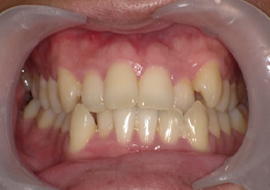

症例1

Before

After

| 主訴 | 上前歯の突出を治したい (出っ歯を治したい) |

|---|---|

| 年齢 | --- |

| 治療 期間 |

約5ヶ月 |

| 治療 内容 |

インビザラインiGoで上顎のみ治療。 前歯の歯と歯の間をごく少量削り、 前に出ている歯が入るスペースを作り、綺麗に揃えた。 |

| 治療費 | ¥352,000(税込)+月額調整料 |

| 治療のリスク | 歯と歯の間を削ることでスペースを確保するので、 場合によっては歯が染みる症状が出ることがある。 |